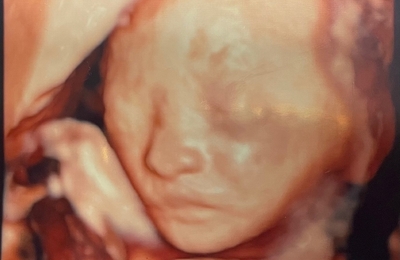

今日でお腹の赤ちゃんが24週を迎えました😊 4Dエコーをしてもらいました♡ 鼻高い😲少し小さめみたいですが、順調との事です♪ 上も子達はみんな4000g程あったので、今回は出来るだけ 小さく産みたい( ゚Д゚) 四人目との事もあり、臨月?という位お腹が出ています(笑) 妊娠前の服は当然入る訳がなく、マタニティー用の服を着ています♡ 腰痛、恥骨痛、頻尿、便秘、肌荒れ、足のむくみ… そして体重増加(笑…